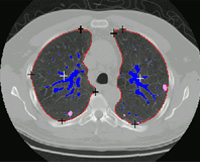

- 我们开发出自动检测和测量结核生长的方法生长测量对肺癌筛选至关重要,但目前使用耗时、不准确和前后不一人工法制作。帮助诊断肺癌很重要,因为及早检测并剖析小生长脉冲可以提高患者5年生存率从15%提高至67%

- 在这个持续项目中,我们开发方法对齐医学图像数据集解剖结构注意力集中在胸口结构注册上,如肺面和肺膜结核方法使用僵化变形体变换